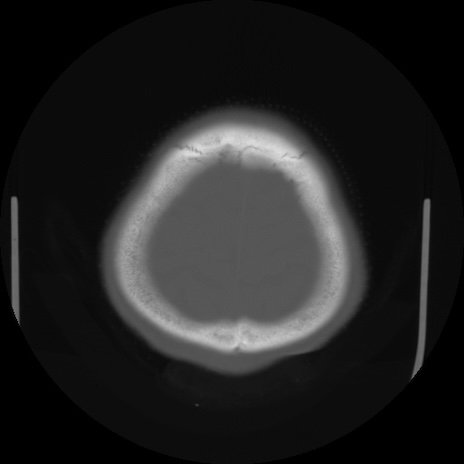

CT(矢状断像)